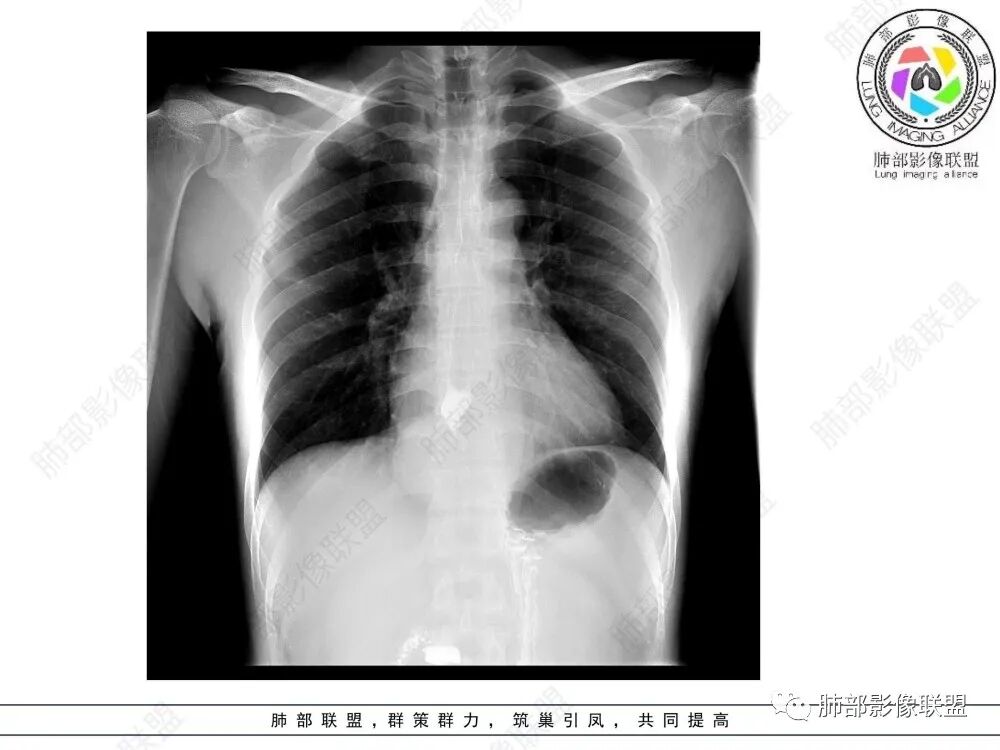

食管下段肿块,环壁生长,分叶状,密度比较均匀,钡餐造影食管下段弧形受压移位,并可见龛影,考虑为食管平滑肌瘤或食管结核。

后面造影图,像腔外  南边老师看得仔细

造影虽然像外压,但是ct肯定更清楚,看ct就是一个环绕管壁生长,管腔狭窄,定位应该没有问题,但是大家病理都答对了,太厉害了

食管平滑肌瘤是最常见的食管良性肿瘤,多见于男性,男女之比为2.6:1,高发年龄 30~60岁之间与食管癌相比,食管平滑肌瘤 的一个主要特点是病史相对较长,病情进展缓慢。病史最长者达10年余,平均 15.7个月,尽管病史较长,但大多数患者仍能进普食。食管平滑肌瘤的诊断一般比较容易,结合患者临床症状、食管造影及食管镜所见,一般均能得出正确诊断。食管造影主要为充盈缺损,病变与食管壁成锐角,粘膜线连续无破坏,管腔收缩扩张比较自如。钡餐造影敏感性高,但对食管壁间及食管周围情况难以判断。CT具有极高的密度分辨率,并且可以获得高质量的多平面重组图像,有利于食管壁间及食管周围情况的判断,表现为食管下段环绕管壁生长,偏心性或薄厚不均软组织密度肿块,密度均匀,内缘分叶状,管腔与正常食管壁构成不规则多角形扩张,增强动脉期无强化,多角度重建其病灶长轴与食管长轴不一致。由于食管壁在收缩状态下厚度约为5.6mm,扩张状态厚度不超过3mm,CT扫描时保持食管处于扩张状态可提高小病灶检出率。MR表现为T1加权等信号,T2加权稍高信号,可见高信号粘膜层,增强扫描轻度渐进性强化,密度均匀,无出血坏死。对于粘膜及周围脂肪间隙的判断具有明显优势。